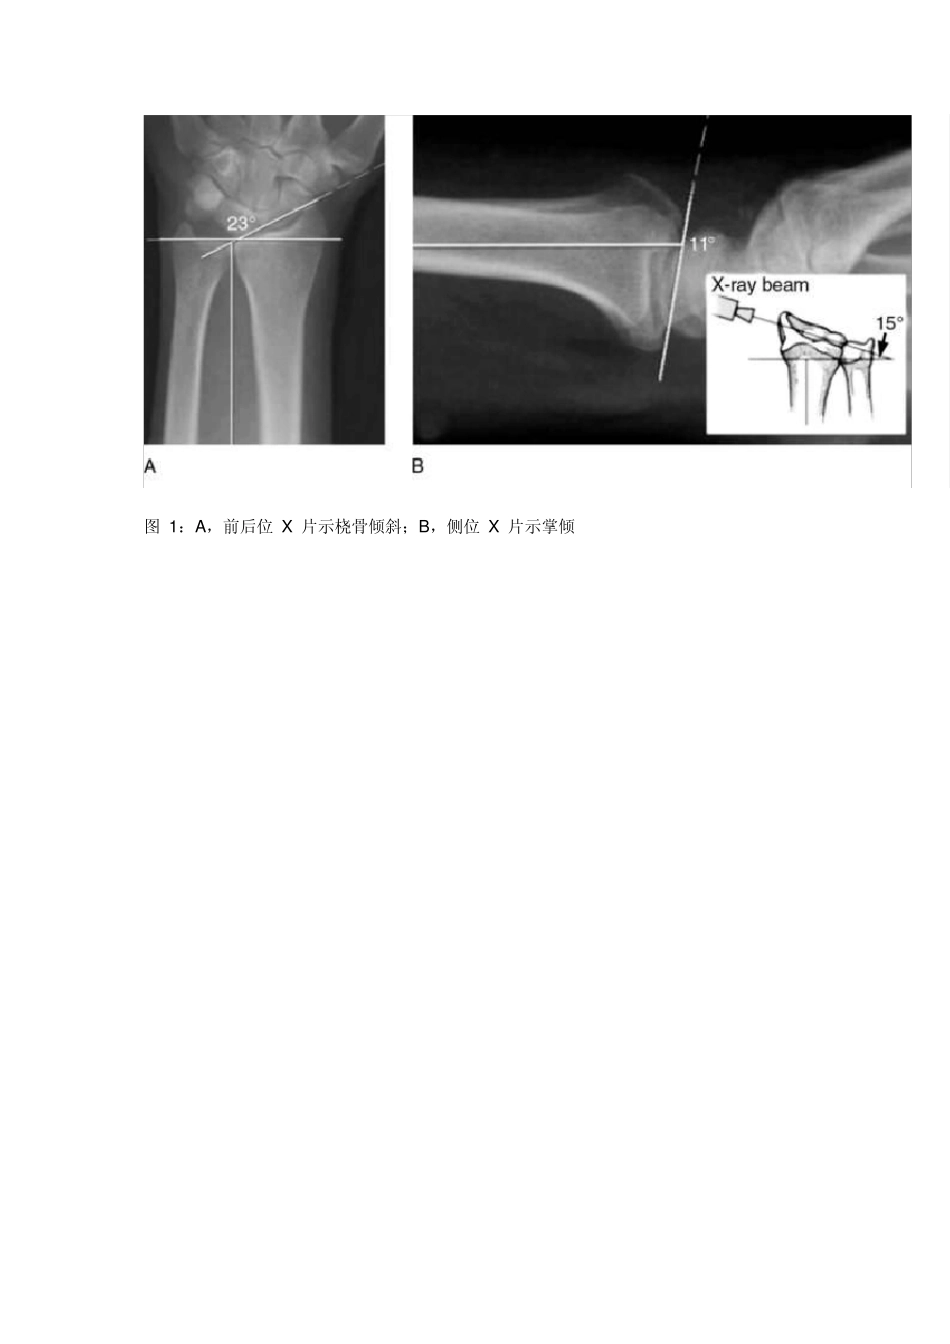

JAAOS 综述:桡骨远端骨折治疗争议 桡骨远端骨折在日常诊疗过程中较为常见,国内现在的治疗趋势是对能耐受手术的中青年患者基本会建议手术;而对腕关节功能要求较低的患者,则手术或者非手术治疗基本接近。 尽管笔者对上述观察结果的总结并不一定正确,但也从侧面证明一个问题,即现阶段桡骨远端骨折治疗仍争议重重。在 2014 年 9 月份的美国 JAAOS 杂志上刊登了目前桡骨远端相关的争议点,包括诊断,影像学评估,治疗和预后等方面,现将中文翻译版呈现给各位,以供在临床实践中参考。 文末会给各位推荐数篇桡骨远端治疗的相关指南和病例介绍,是早先丁香园骨科频道译者(@第五十七回 )对 AAOS 桡骨远端骨折治疗指南的解读,欢迎各位点击阅读。 桡骨骨折相关的问题,包括桡骨骨折评估,诊断,治疗及功能预后的评估等极富争议。各种影像学检查手段在评估桡骨骨折中的准确性均未得到确实有效的证实。此外,桡骨远端的分类方法多样,大部分分类方法在不同观察者间及同一观察者内的可靠性也存在较多疑问。 非手术治疗桡骨远端的主要争议点在于骨折的复位,麻醉的使用,骨折的制动时间,前臂在骨折愈合过程中的位置等。手术治疗桡骨远端骨折的争议点包括手术指征,术后出现腕管综合征需要再次手术减压,骨折固定的方法,骨折固定是否需要加强。桡骨骨折术后的康复策略,用药,物理锻炼方法等也存在较多争议。目前临床上对桡骨远端骨折的临床功能预后使用何种标准评估尚无统一的意见。上述所有争议内容后期需要更多的临床研究进行进一步的评估。 桡骨远端骨折在临床中较为常见,其年发生数量为 60 万例。其发病年龄呈现双峰的特点,即以高能量损伤的年轻人和低能量损伤的老年人为主体。2007 年,美国桡骨远端骨折的医疗花费接近 1.7 亿美元。 对桡骨骨折采取合适的治疗方案要求临床医生准确的评估骨折形态,诊断,治疗,并熟悉术后功能恢复评估方法。桡骨骨折诊断,治疗,术后评估等均存在较多争议。2009 年美国 AAOS 协会发布了第一版的桡骨远端骨折治疗指南,但是上述指南的临床证据并不充分。 争议点:骨折评估 临床上有很多方法可以评估桡骨远端骨折。前后位,侧位,斜位 X 片等可以评估桡骨的倾斜,长度和掌倾角(图 1)。前后位 X 片清晰的桡骨远侧边缘和侧位片上清晰的泪滴样桡骨远端是正常的解剖学表现。在前后位 X 片上,桡骨远端背侧边缘投影要超过桡骨近端骨皮质约 3-5m m 。侧位片时,泪滴点的切线和...